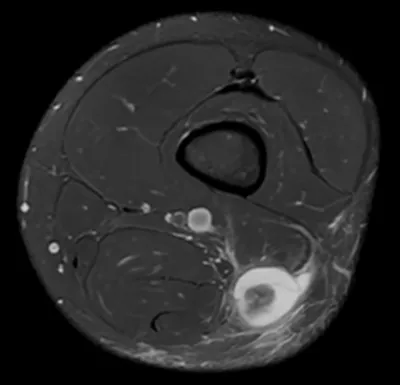

Torn long head of biceps femoris - BAMIC grade 4

MRIAxialThigh+1

2/10/2026